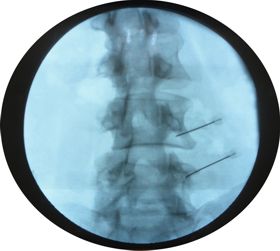

Vertebroplastía

Es un tratamiento mínimamente invasivo, no quirúrgico, guiado por imagen. Tiene como fin reforzar una vértebra fracturada, de forma patológica (generalmente  por osteoporosis) y menos frecuente por neoplasia.

Permite mejorar la capacidad funcional y prevenir el colapso del cuerpo vertebral. Sirve además para paliar el dolor debido a la fractura compresiva. Se basa en inyectar cemento ortopédico a través de una aguja en el hueso fracturado.to

El procedimiento involucra colocar una pequeña aguja dentro del hueso fracturado. El cemento para hueso se inyecta dentro del mismo para asegurarlo. En algunos casos se pueden atender varios huesos al mismo tiempo.

El médico es el responsable de guiar la aguja a la posición correcta usando un equipo especial de rayos X. Por lo tanto, no se requiere cirugía abierta.